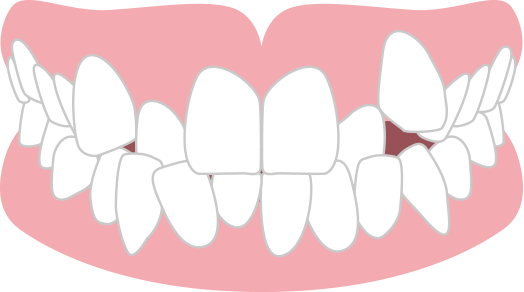

受け口 下顎前突

下の歯が上の歯よりも前に出ている状態。

咬み合わせが悪く、発音(特にサ行)にも問題が生じます。さらに下あごが突出したお顔つきになります。重度の受け口の場合は矯正歯科治療が保険適用になります。